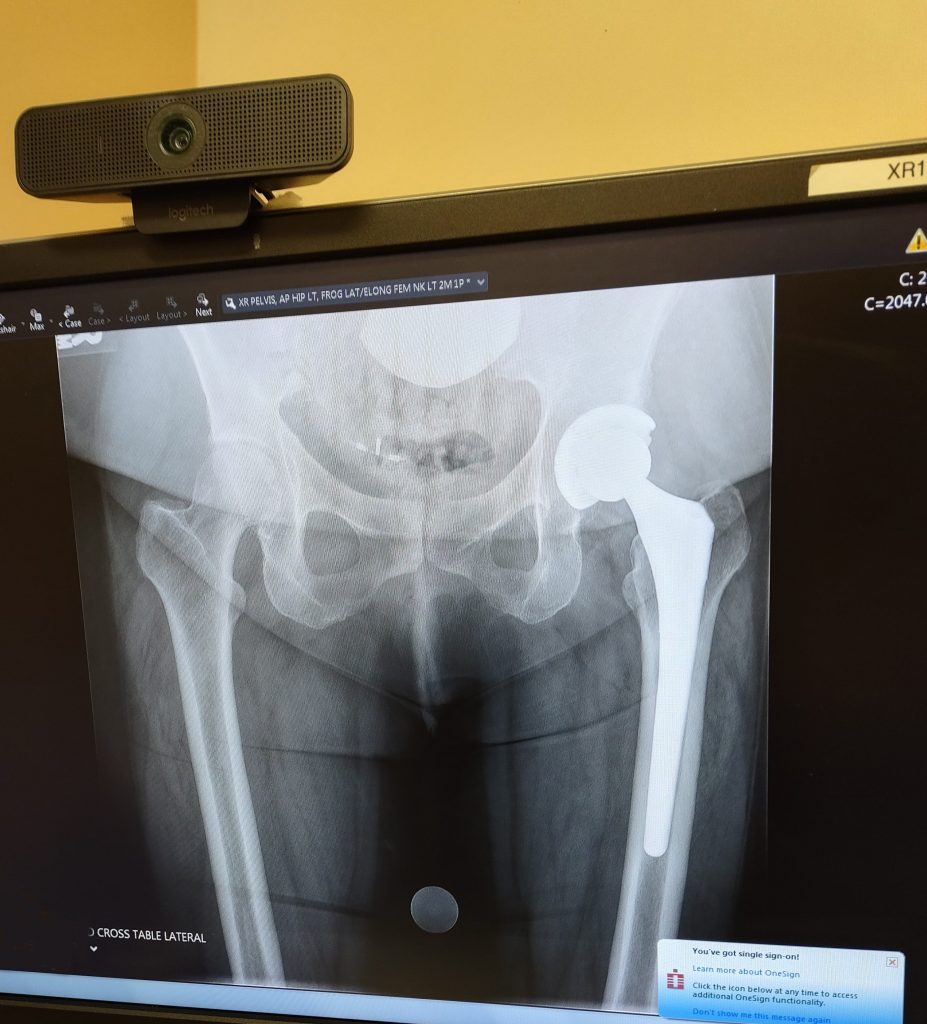

I knew HSS was the best I had heard! I called, made a appointment, got some x-rays, and was told by my physicians that they would definitely help me. They scheduled my hip replacement surgery right away.

The ambulance came and transported me within an hour. I was checked in to my room and saw Dr. Aleksey Dvorzhinskiy that evening after I arrived. He had just finished another surgery and he was confident, kind, caring, smart and responsive to my needs. He reviewed my x-rays and scheduled my surgery.

Later that night, Dr. Dvorzhinskiy came to my room to visit with me and went over my new x-rays the next day. He showed me all the hardware that was inside my ankle and knee.